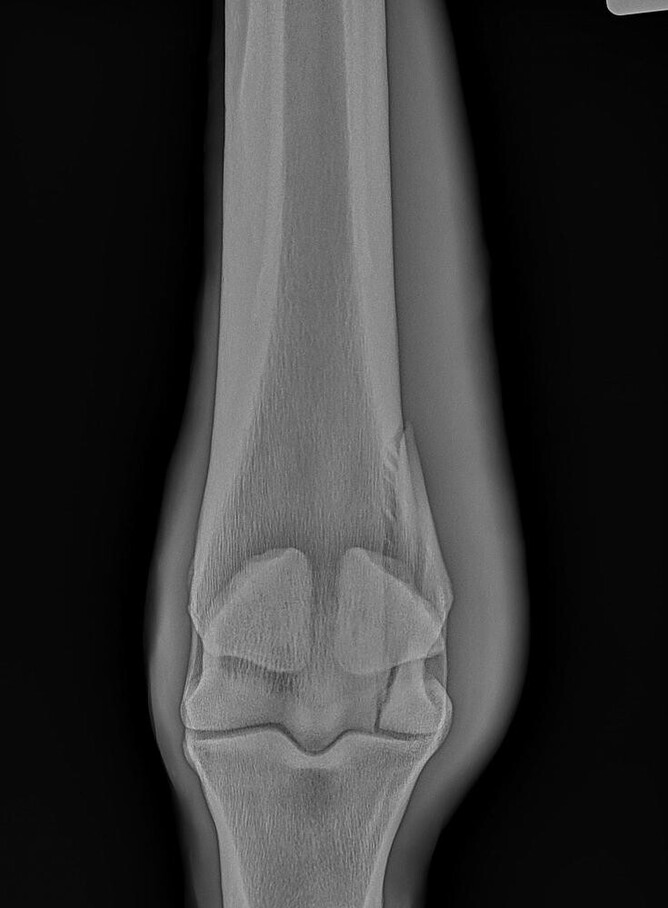

The repair of the fracture shown in Figure 2 was performed on a standing horse. The finished repair is in Figure 3. Figure 4 shows standing screw placement into a knee fracture.